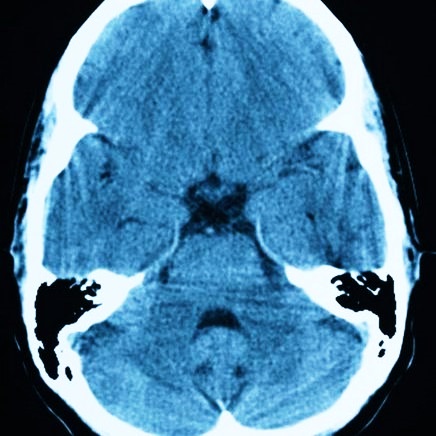

На сегодняшний день основными методами диагностики и последующего прогноза данной болезни являются МРТ (магнитно-резонансная томография) и КТ. Полученная томограмма показывает состояние всех составляющих мозга (эпифиза, мозжечка, гипофиза, нервных ганглий и других частей). С ее помощью можно увидеть место расположения перивентрикулярного глиозного очага и атрофических рубцовых следов внутри головного мозга без вскрытия черепной коробки, оценить их форму, размеры и интраселлярный рост.

Кроме того, данные способы обследования позволяют сделать дифференциальную диагностику промежуточного состояния между доброкачественной кистой и злокачественной опухолью. После внутривенного введения специального контрастного вещества его продукт накапливается в опухолевых тканях, а киста при этом не становится контрастной.

Также нередко проводится эндоскопия и доплеровское ультразвуковое сканирование кровеносных сосудов с целью исследования их состояния, кровоснабжения тканей мозга, выявления локализации ишемии, в которой и активизируется образование кист.